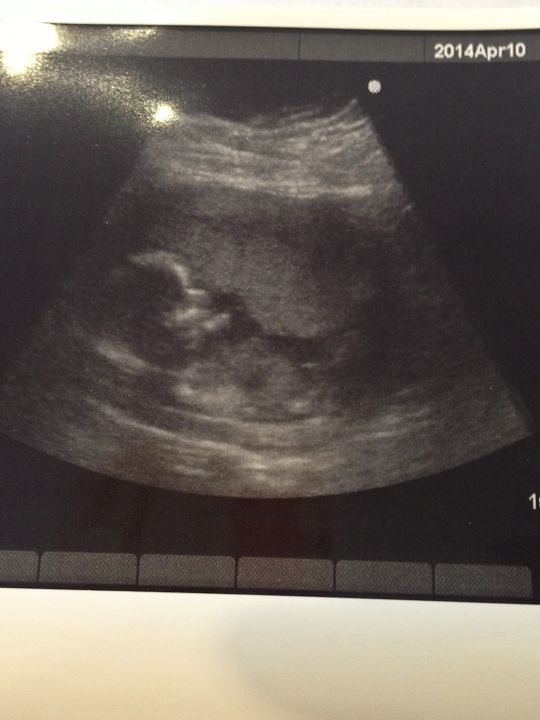

I had a doctor appointment last Thursday. Stephen went with me and we took Stephen. The nurse was having a hard time finding the heartbeat with the doppler so we got to have an ultrasound. I was so happy because Stephen didn't go to my last appointment when I had an ultrasound and it was so neat to show Stephen the baby. And of course I loved seeing my baby! I wish I could have an ultrasound at every appointment!

Best Moment this week: Seeing our baby!